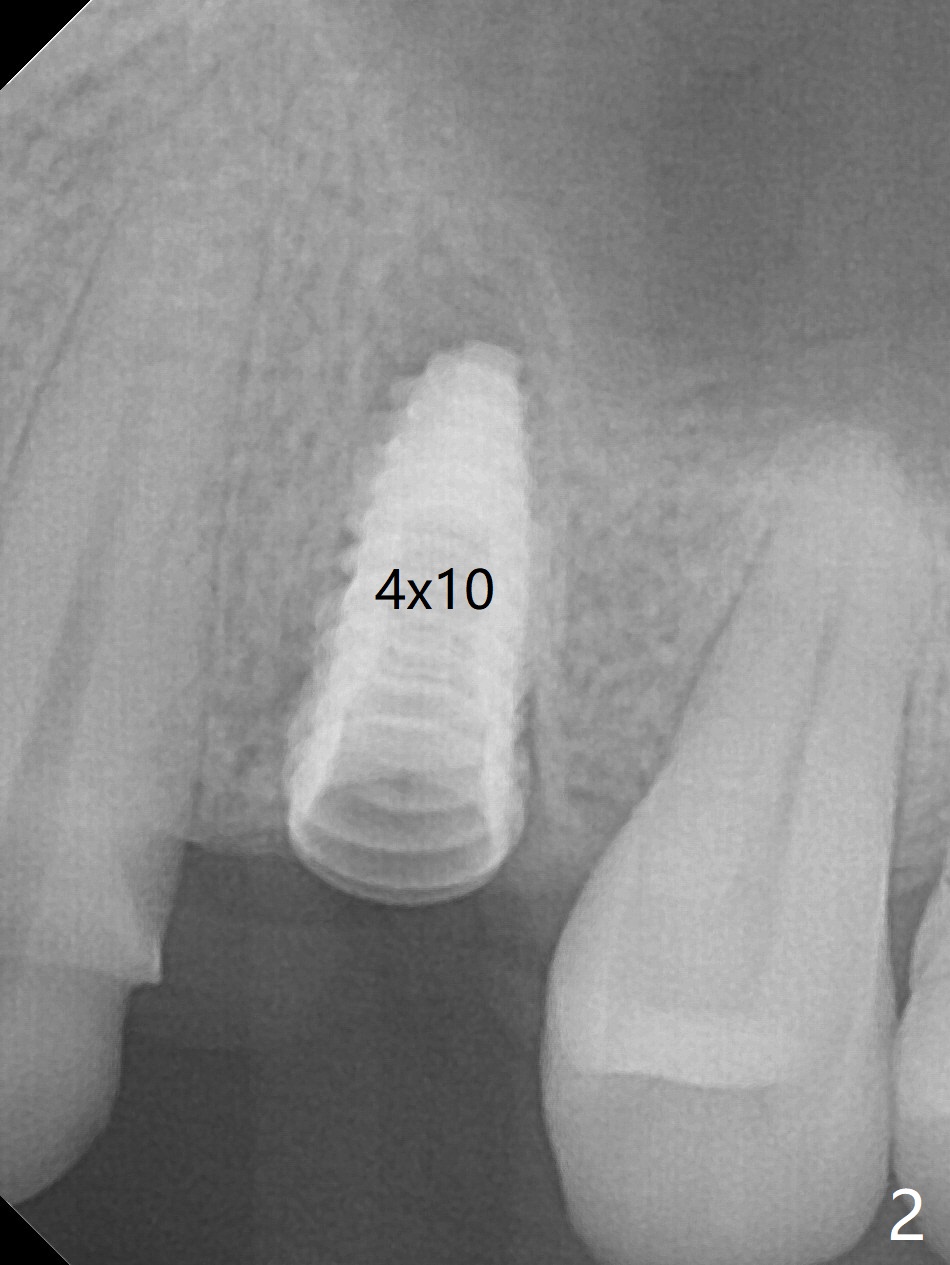

After extraction of the residual roots at #12 and crown prep at #11, osteotomy at #12 is established with Pointed Lindamann bur and 2.2 mm bur for ~ 15 mm. There feels to be sinus floor perforation; a parallel pin is inserted deeper than expected (Fig.1), but there is no membrane perforation. Following sequential osteotomy, a 4x10 mm dummy implant is placed partially with stability (Fig.2). When the same sized definitive implant is placed subcrestally (Fig.3-5 (*: Vera Graft)), the stability remains (~60 Ncm) in spite of the fact that the trajectory is changed once. The coronal socket does not seem to heal 8.5 months postop, in part due to poor hygiene of splinted provisional (Fig.6).